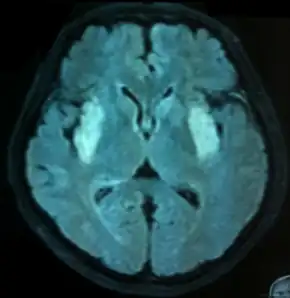

Bilateral contrast hyperintensity in medial temporal lobes of individual with anti-NMDA receptor encephalitis.

First and foremost is high level of clinical suspicion especially in young adults showing abnormal behavior as well as autonomic instability. The person may have alteration in level of alertness and seizures as well during early stage of the illness. Clinical examination may further reveal delusions and hallucinations.